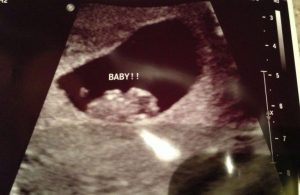

이 방법은 임신 초기 최초의 초음파를 통해, 사진에 나온 태반의 위치를 보고 태아의 성별을 맞추는 것이다.

임신 4주가 지나면 태아의 팔, 다리가 발달하기 시작한다. 그리고, 램지법은 임신 8주 전에 찍힌 초음파 사진을 통해 태아의 성별을 알 수 있게 해준다.

발달 초기 단계 중, 성기는 구분하는 것이 거의 불가능하다. 이것이 바로, 램지법이 그토록 높은 유명세를 얻게 된 이유이다. 태아의 성별을 좀 더 정확하게 알 수 있는 때는 임신 20주 이후에 찍는 초음파 사진이다.

초기 단계에 태아는 태반에 매우 가까이 붙어 있게 된다. 가장 중요한 것은 밝은 부위를 찾는 것이다. 이미 진행된 유사한 종류의 연구를 참고하는 것 또한 필요하다. 융모막 융모의 위치는 사용하는 초음파의 종류에 따라 달라진다.

질 초음파 또는 복부 초음파를 사용할 수 있다. 정확하지도 않은 방법을 사용해 태아의 성별을 짐작하는 쓸데없는 시간 낭비를 하지 말자.